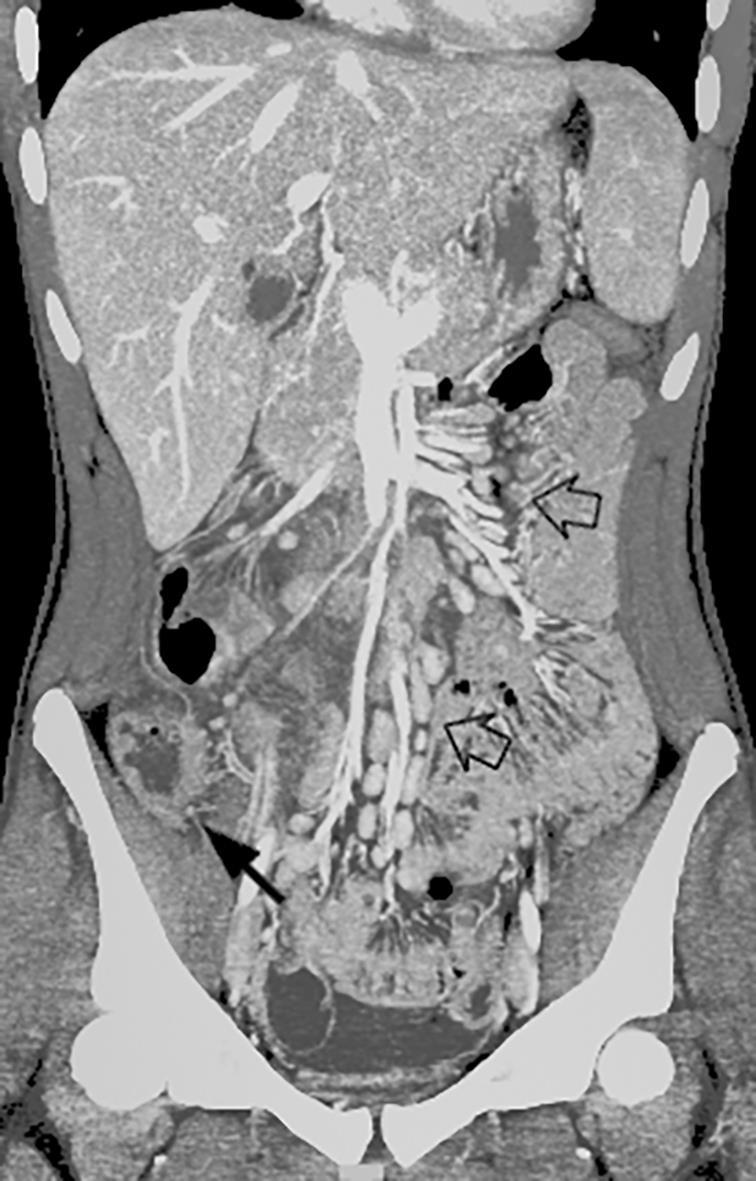

Abdominal abnormalities

Solid viscera abnormalities

Hepatomegaly

Echogenic kidneys

Splenomegaly

Hollow viscera abnormalities

Gallbladder wall thickening

Bowel wall thickening

Bowel dilation

Gastric distention

Urinary bladder thickening

Peritoneal abnormalities

Small ascites

Mesenteric abnormalities

Mesenteric lymphadenopathy

• Gastrointestinal (GI) symptoms (abdominal pain, diarrhoea and vomiting) are prevalent in MIS-C

• Abdominal pain in 62%

• Up to 90% any GI symptom

• Anumber of studies have described abdominal imaging findings including ascites, bowel wall thickening and mesenteric lymphadenopathy